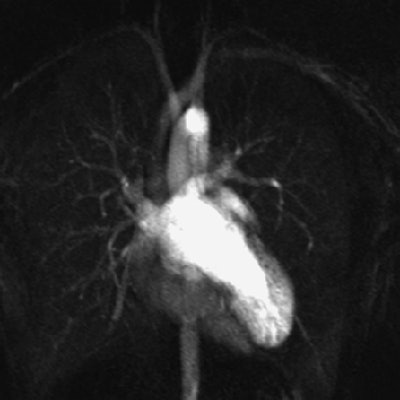

| Fig. A (above), 23-year-old woman referred to MRI with suspicion of transposition of great arteries because of prominent trabeculation of subaortic ventricle in echocardiography. Time-resolved coronal maximum-intensity-projection angiograms (B-C, below) and cine short-axis view (D, bottom). The angiograms show normal time course of enhancement of subpulmonary atrium and ventricle and pulmonary arteries (A); and enhancement of pulmonary veins, subaortic atrium, ventricle, and aorta (B). Note decreasing enhancement of subpulmonary ventricle from A to C, indicating absence of relevant left-to-right shunt flow. This patient suffered from noncompaction myocardium, which is visualized on time-resolved MR angiography (C) (arrow) and is shown on cine short-axis view (D) (arrows). Republished with permission of the American Roentgen Ray Society from AJR 2006; 187:1107-1114. |